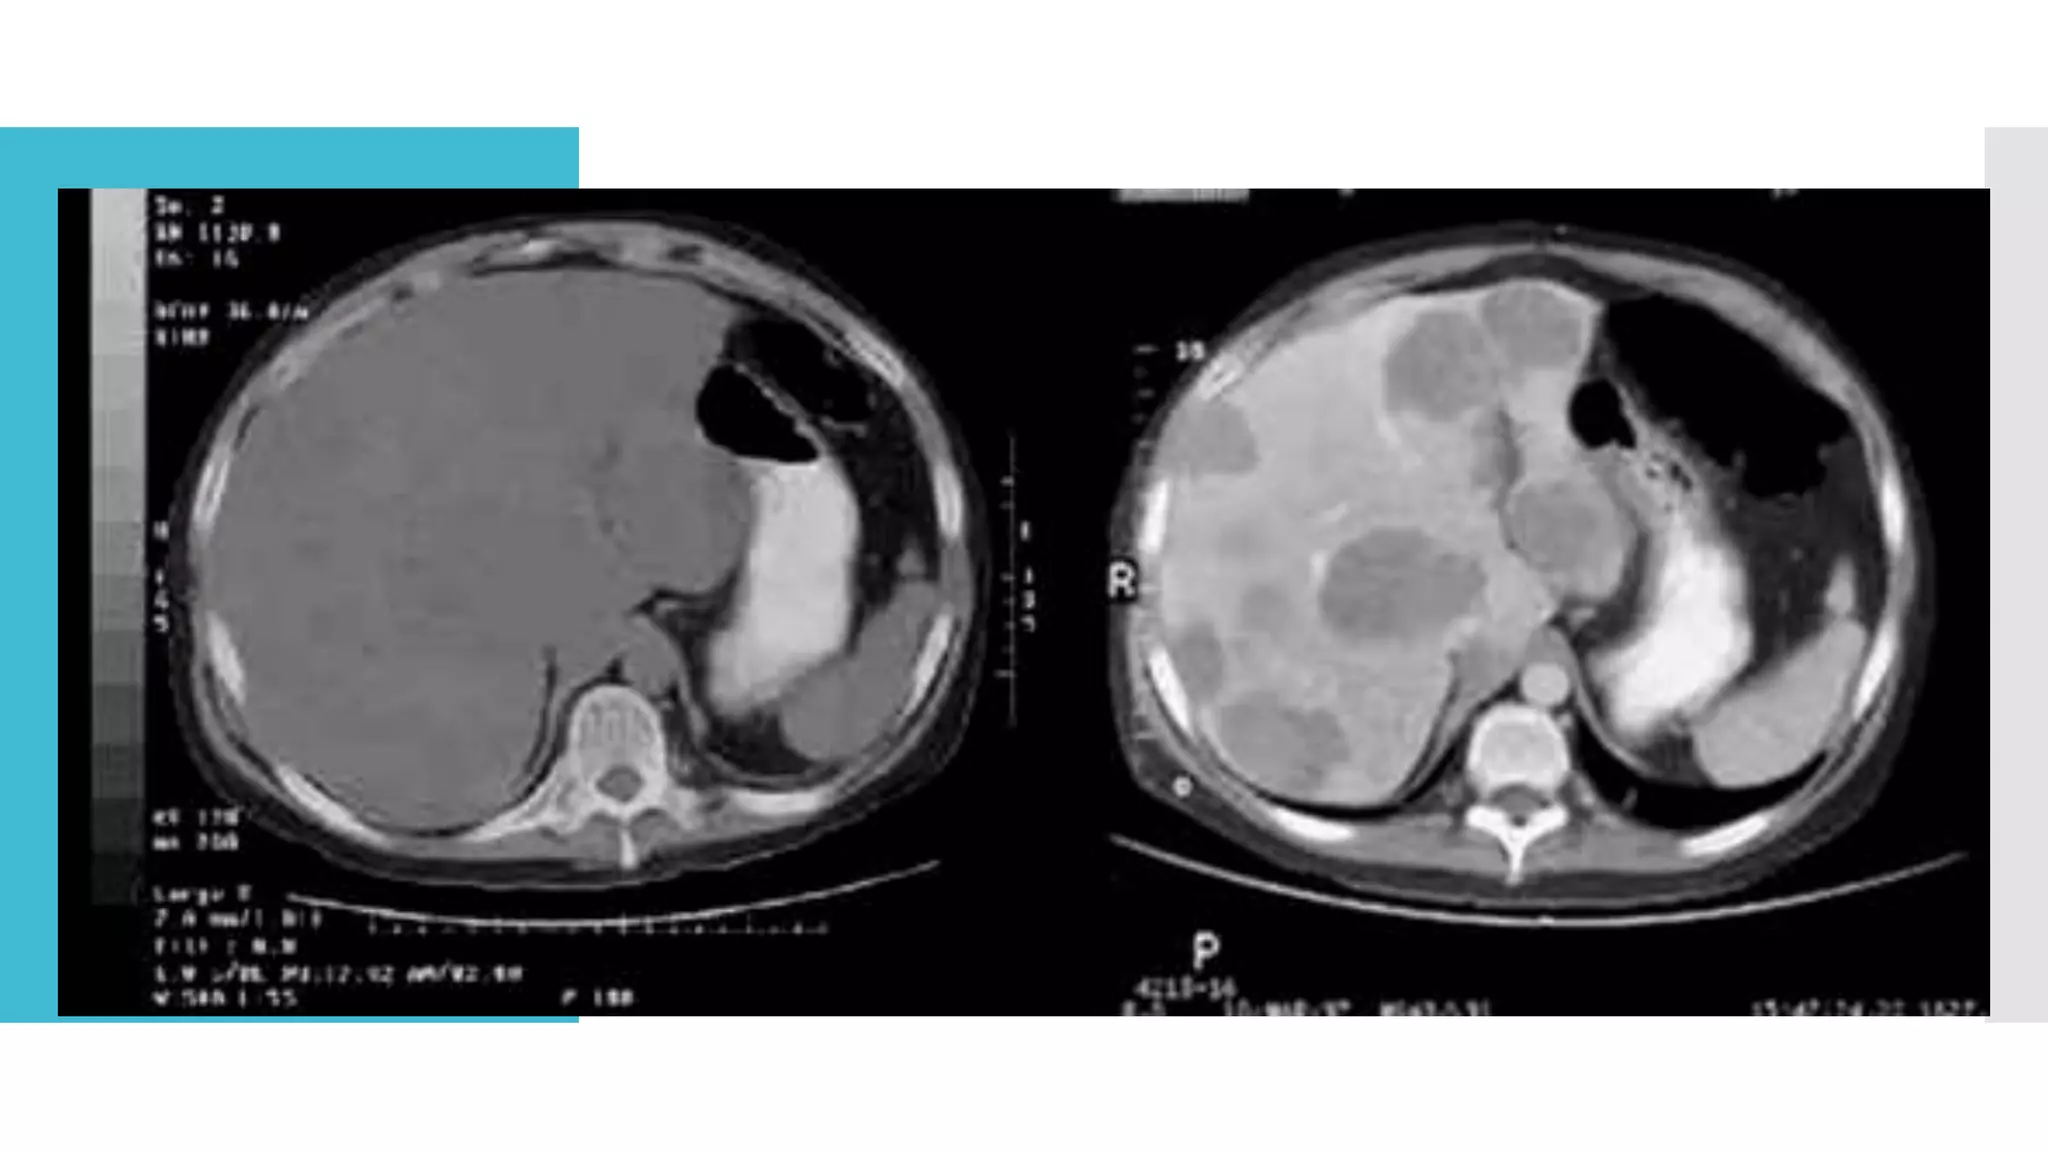

Cystic lesions:

 Simple cysts should not be considered as malignant

lesions

(neither measurable nor non-measurable)

 If noncystic lesions (i.e solid )are present in the same

patient, these are preferred for selection as target

lesions.

 Cystic lesions’ thought to represent cystic metastases

can

be considered as measurable lesions, if they meet the

definition of measurability described above.

Special considerations Cystic lesions:  Simplecysts should not be considered as malignant lesions (neither measurable nor non-measurable)  If noncystic lesions (i.e solid )are present in the same patient, these are preferred for selection as target lesions.  Cystic lesions’ thought to represent cystic metastases can be considered as measurable lesions, if they meet the definition of measurability described above.